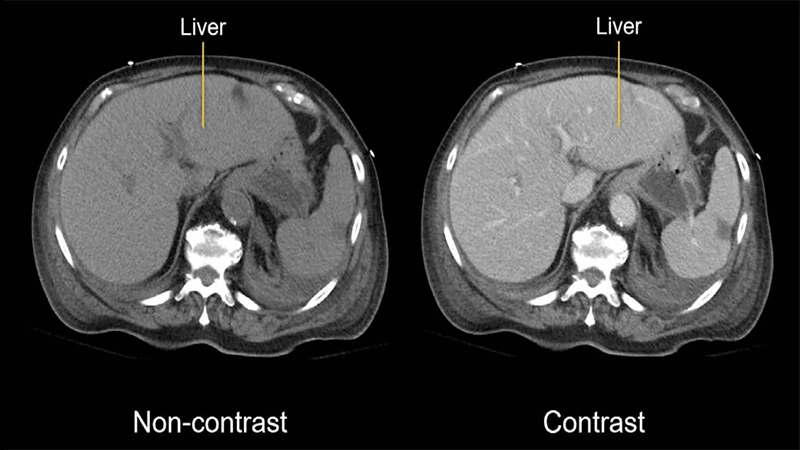

A side-by-side comparison of an abdominal CT scan without contrast and one with IV contrast, showing enhanced detail of the organs and vessels.

• How it Works: When injected into a vein, the iodine-rich fluid travels through the bloodstream, causing blood vessels and highly vascular organs (like the liver and kidneys) to appear bright white on a CT scan. This allows for detailed evaluation of arteries and veins (CT Angiography) and helps identify abnormalities like tumors, which often have a different blood supply than normal tissue.